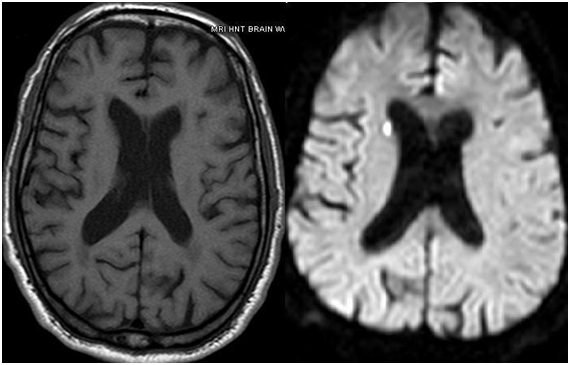

Plasma exchange was initiated immediately along with systemic steroids. Platelets counts improved, the patient remains afebrile and hemodynamically stable but his altered mental status persisted. Further workup for his persistent change in mental status revealed multiple bilateral acute lacunar infarcts on Magnetic Resonance Imaging (MRI) of the Brain as shown in Figure 2, which is likely embolic in etiology.

Figure 2 Axial DWI Magnetic Resonance Imaging of the Brain with and without contrast showing acute lacunar infarct.